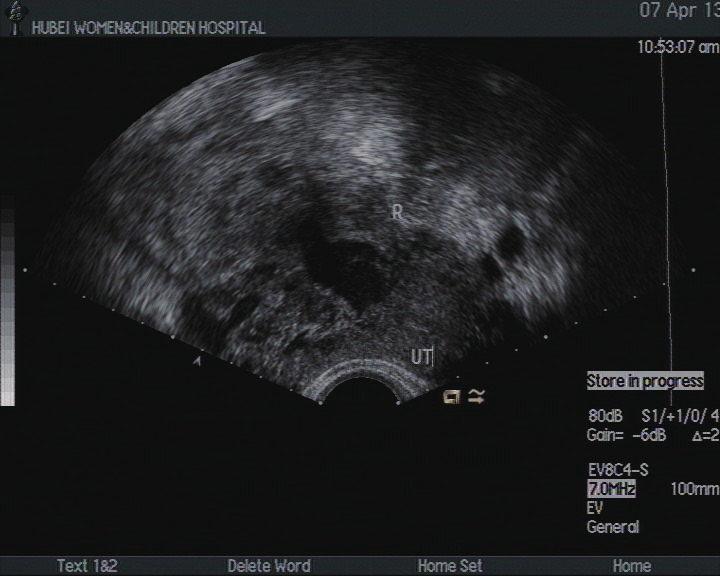

超声检查  2013 年 4 月 2 日,子宫切面形态失常,大小 7.1cm ×4.9cm ×5.2cm ,边界清,肌层光点分布不均匀。子宫左后壁可见 3.7cm ×4.2cm ×3.6cm 的低回声,边界清,向外突,周边可见血流信号,测得 RI:0.23。右侧角部可见 7.1cm ×9.0cm ×8.0cm 的低回声,其内回声不均并可见多个不规则的无回声,其中一个大小为 4.0cm ×2.3cm ;其中低回声内可见丰富的血流信号,测得 RI:0.32。内膜可显示,厚度 0.32cm ,内未见明显异常血流信号。彩色多普勒:肌层血流可显示。右侧卵巢因肠干扰显示不清。左侧卵巢内可见多个无回声,其中最大一个为 3.1cm ×2.5cm 。宫颈前后径 2.9cm 。陶氏腔内见 1.1cm ×2.3cm ×1.0cm 的液性暗区。提示:子宫声像图改变(子宫肌层侵蚀性病灶可能);左侧卵巢囊肿;陶氏腔少量积液。

图B 超声图像(2013 年 04 月 02 日,化疗前)